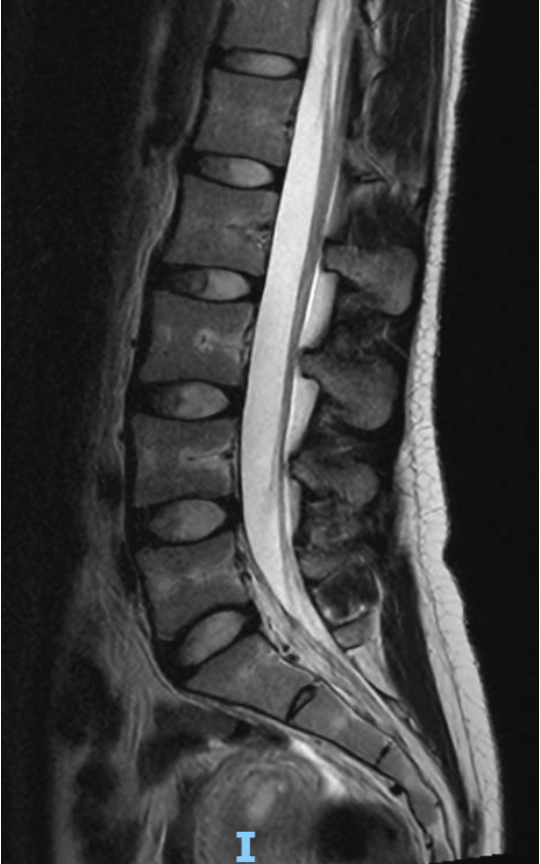

Lumbar Spine Anatomy

A normal lumbar MRI shows healthy discs, well-aligned bones, and open spaces for the nerves. There is no significant nerve compression or structural damage.